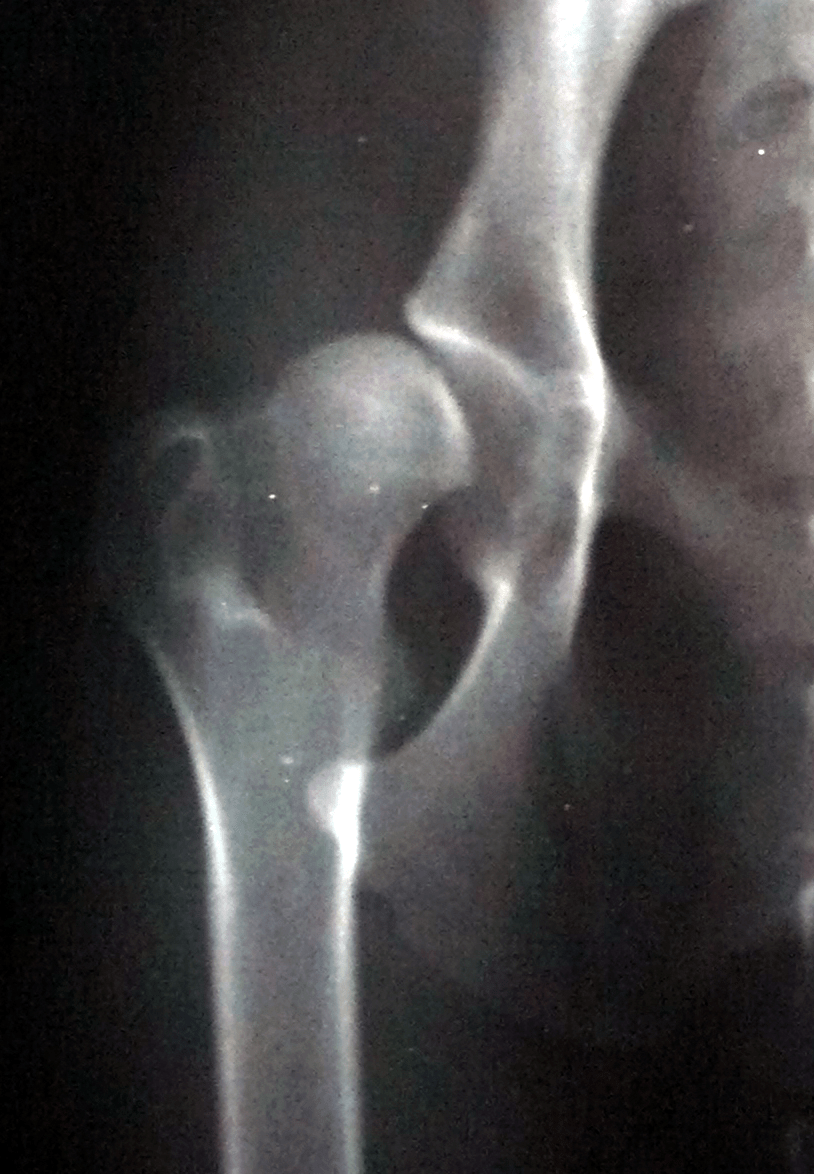

- al ligamento redondo del codo;